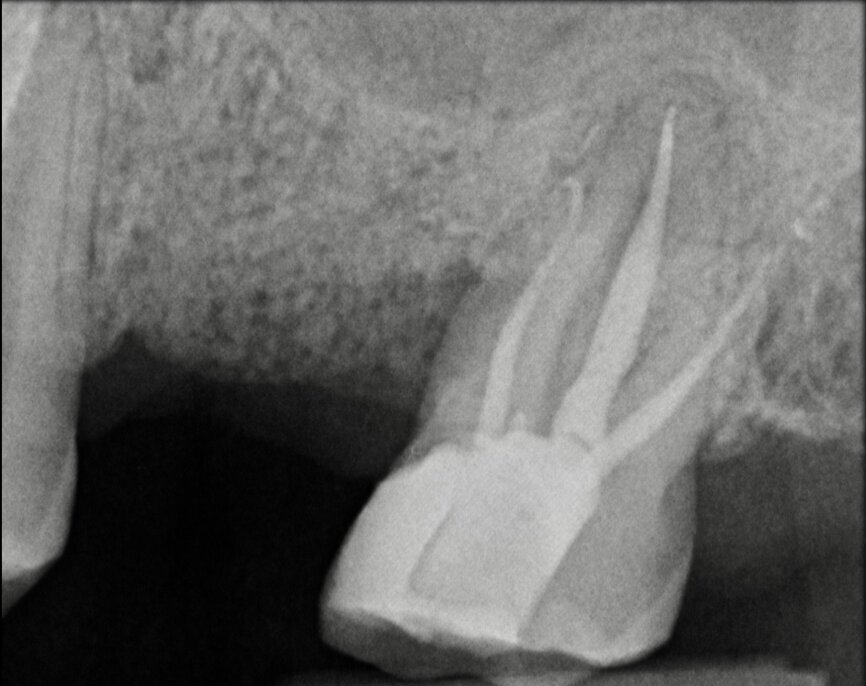

The situation was entirely different for the mandibular premolar shown in Figures 7 to 9, where, in the absence of any radiological signs of a lesion and despite the apparently correct endodontic approach adopted by another colleague, the patient complained of persistent pain which was both spontaneous and triggered by percussion of the tooth. In this case, the previous excellent root canal therapy would suggest an endodontic surgery approach, which could guarantee a higher success rate than retreatment. Given this diagnostic doubt, it was decided to perform a 3D study, which revealed an endodontic lesion caused by an untreated lingual canal. This correct diagnosis, thus, made it possible to perform selective intervention on the remaining pulp, leading to successful treatment of the untreated canal.